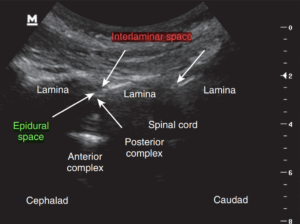

نخاع در تمام طول ستون فقرات، در داخل مهرهها و توسط سه لایه محافظ احاطه شده است.

خارجیترین لایه، دورا (Dura) نام دارد.

به فضای بین این لایه و سطح داخلی مهرههای ستون فقرات، فضای اپیدورال گفته میشود که با بافت چربی و عروق کوچک پر شده است.

در تصاویر زیر، این فضا با هایلایت سبز مشخص شده است.

به دلیل نزدیکی فضای اپیدورال به نخاع، میتوان برای بلاک اعصاب نخاعی (اعصابی که مستقیماً از نخاع خارج میشوند) داروهای بیحسی را به داخل این فضا تزریق کرد.